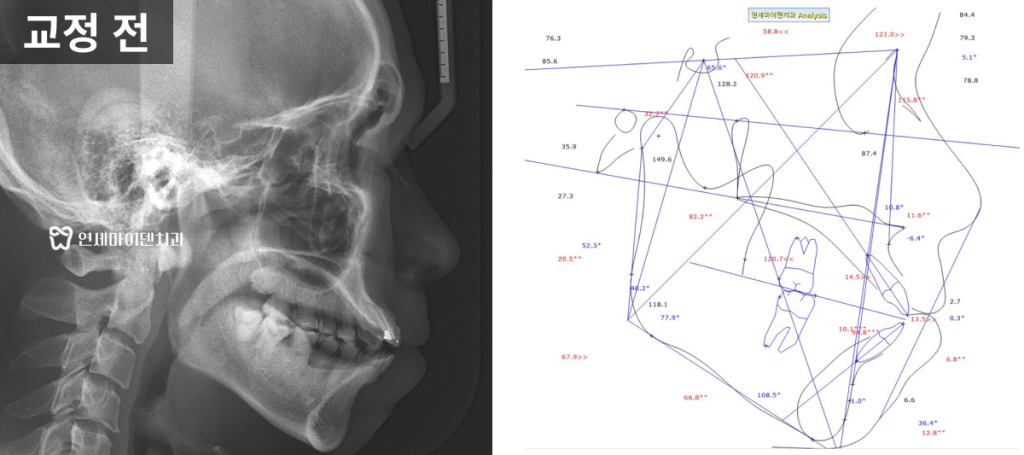

옆모습 방사선 사진을 분석한 결과

위턱에 비해 아래턱이 많이 들어간 2급 부정교합,

흔히 말하는 무턱 형태도 동반되어 있었고,

그로 인해 입술이 돌출되어 보이는 양상이 나타났습니다.

이러한 진단을 토대로 인비절라인 교정을 계획하였습니다.